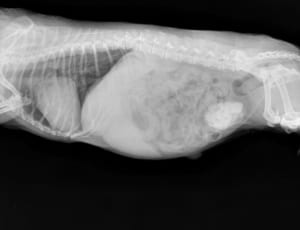

手術はレーザーを用いており、動物に負担が少なく、出血が少ないなどのメリットがあります。

腫瘍切除などの他に、避妊・去勢手術なども行っておりますのでお気軽にご相談ください。